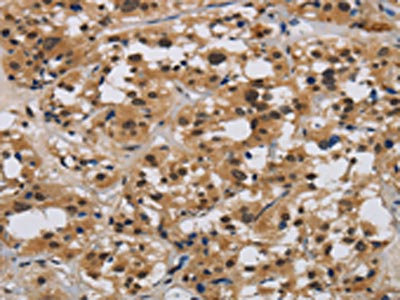

The image on the left is immunohistochemistry of paraffin-embedded Human thyroid cancer tissue using CSB-PA263795(E2F4 Antibody) at dilution 1/40, on the right is treated with synthetic peptide. (Original magnification: ×200)

The image on the left is immunohistochemistry of paraffin-embedded Human liver cancer tissue using CSB-PA263795(E2F4 Antibody) at dilution 1/40, on the right is treated with synthetic peptide. (Original magnification: ×200)